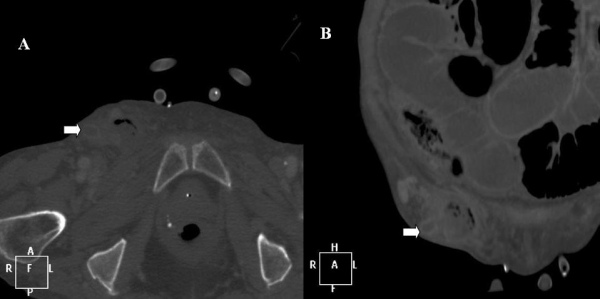

Hình 15: Tắc ruột do lồng ở bệnh nhân nữ 41 tuổi bị nhồi máu và hoại tử túi thừa Meckel. A, các quai ruột non trên đoạn tắc giãn lớn. B, đoạn hồi tràng bị lồng, đoạn ruột non thành dày phù nề (đầu mũi tên). Điểm giữa đoạn lồng có mỡ giảm đậm độ (mũi tên). Sau phẫu thuật : nhồi máu và hoại tử túi thừa Meckel là nguyên nhân gây lồng hồi – hồi tràng. (Angela D. Levy, Christine M. Hobbs (2004). Meckel Diverticulum: Radiologic Features with Pathologic Correlation. RadioGraphics; 24:578)